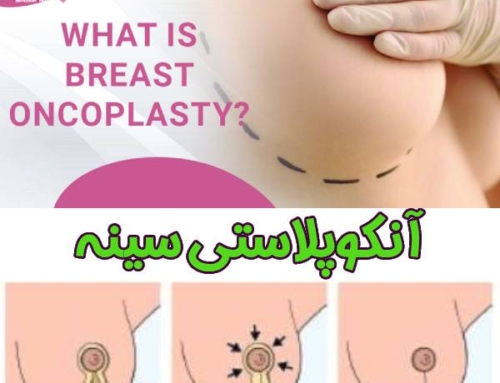

- جراحی با حفظ بافت پستان : هنگامی که تومور سرطان سینه ، کوچک و محدود به قسمتی از پستان باشد ؛ می توان تومور سرطانی را با حفظ بافت پستان برداشت. توجه داشته باشید که این روش درمان سرطان پستان ؛ به درمان های تکمیلی از قبیل پرتو درمانی نیز احتیاج دارد.